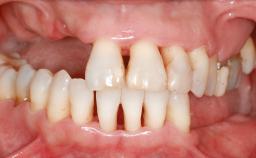

A 20-year-old woman was referred for implant therapy in 2004. Her medical history revealed no significant findings, and neither did she smoke nor take any medications. An extraoral examination revealed no abnormalities of the skin, hair or nails. The intraoral examination revealed only 11 permanent teeth clinically. These were normal in shape, size, and color. In addition, eight retained deciduous teeth (53, 62, 63, 71, 72, 73, 81, 82) were present. No abnormalities were detected during the general examination. The family history revealed that the patient’s father and two sisters were on record with similar conditions. The clinical examination revealed a thick gingival biotype. No recession of the attached gingiva was noted, but the retained deciduous teeth were mobile and unsightly. As a syndrome had not been diagnosed, the case was categorized as non-syndromic oligodontia.

Soft Tissue Anatomy Intact Defective

Bone Volume Horizontally and vertically sufficient Horizontally deficient Deficient vertically or deficient vertically AND horizontally